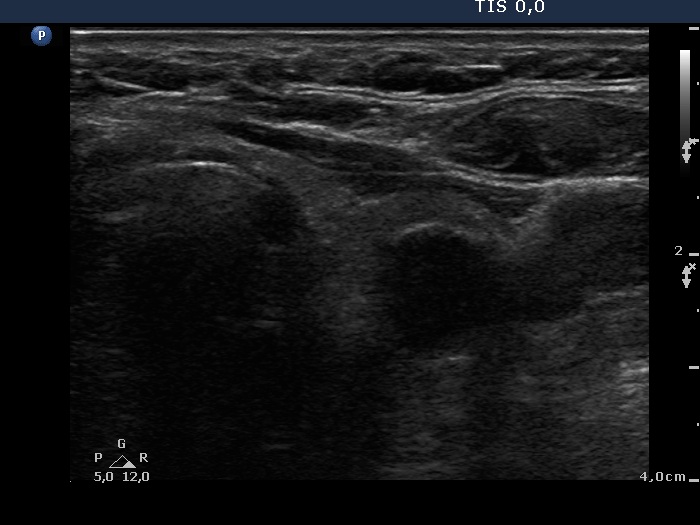

Benign hyperplastic nodule (histological diagnosis) - case 489 |

The nodule had an eggshell calcification.